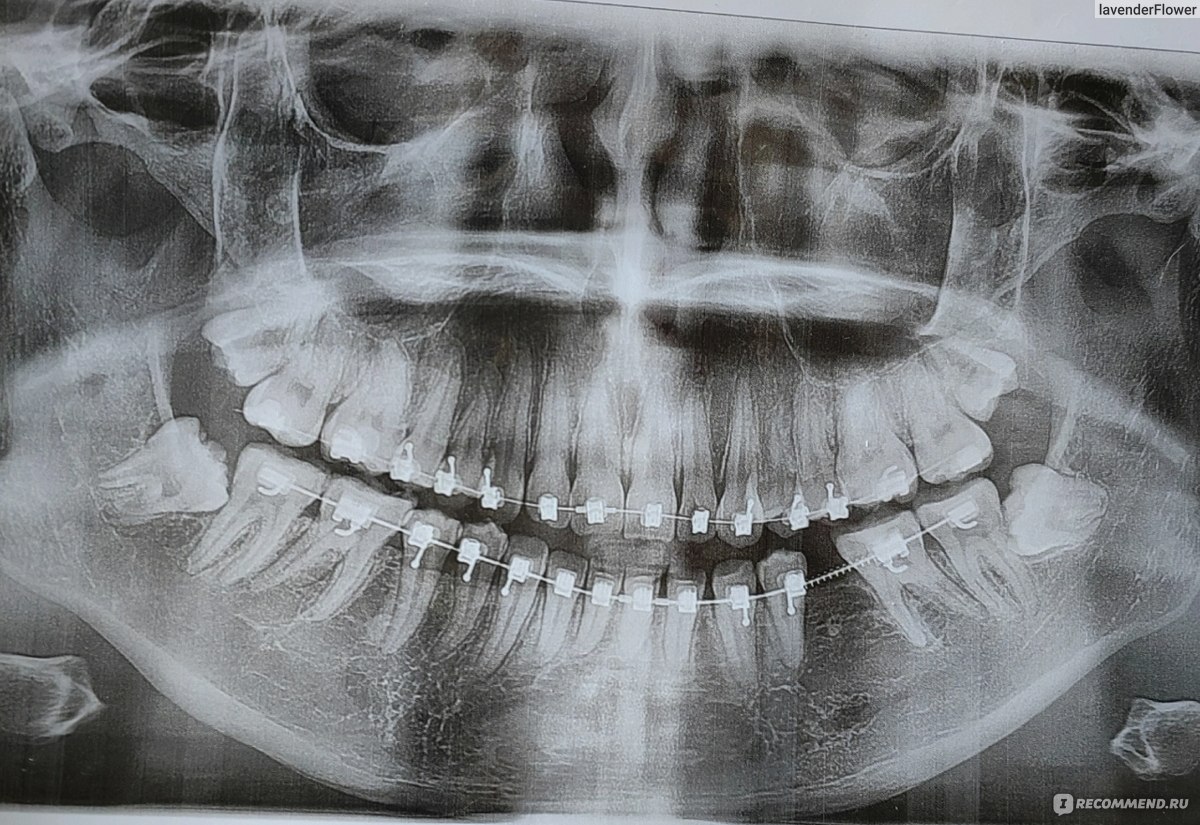

Дентальная галерея: ретинированный зуб клык и его лечение

Раздел: Компас решений